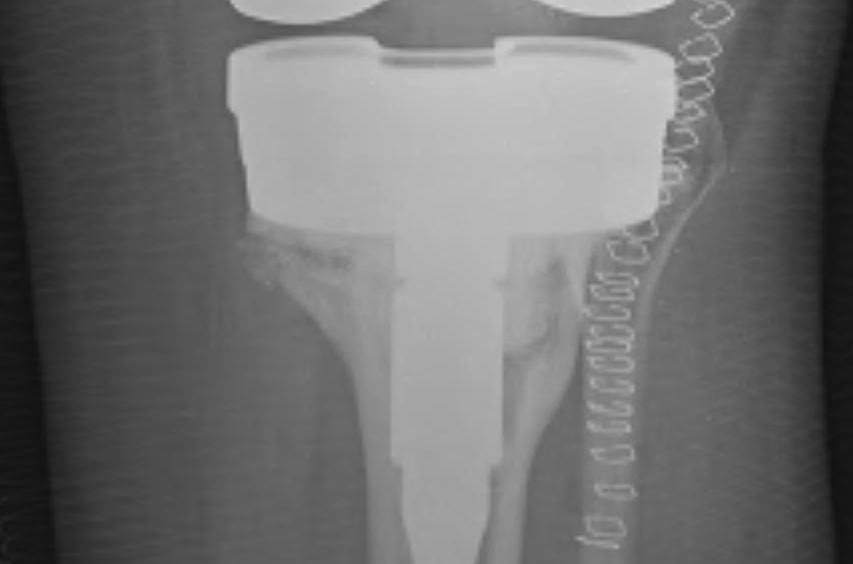

3. Tibial tuberosity osteotomy

- 6-10 cm long, 2 cm wide, 1 cm thick

- lateral periosteum intact / lever open laterally

- bypass osteotomy with stem

- need to wire back around the tibial stem

- place wires before definitive stem

- drill holes medially and laterally

- can use diverging screws as well